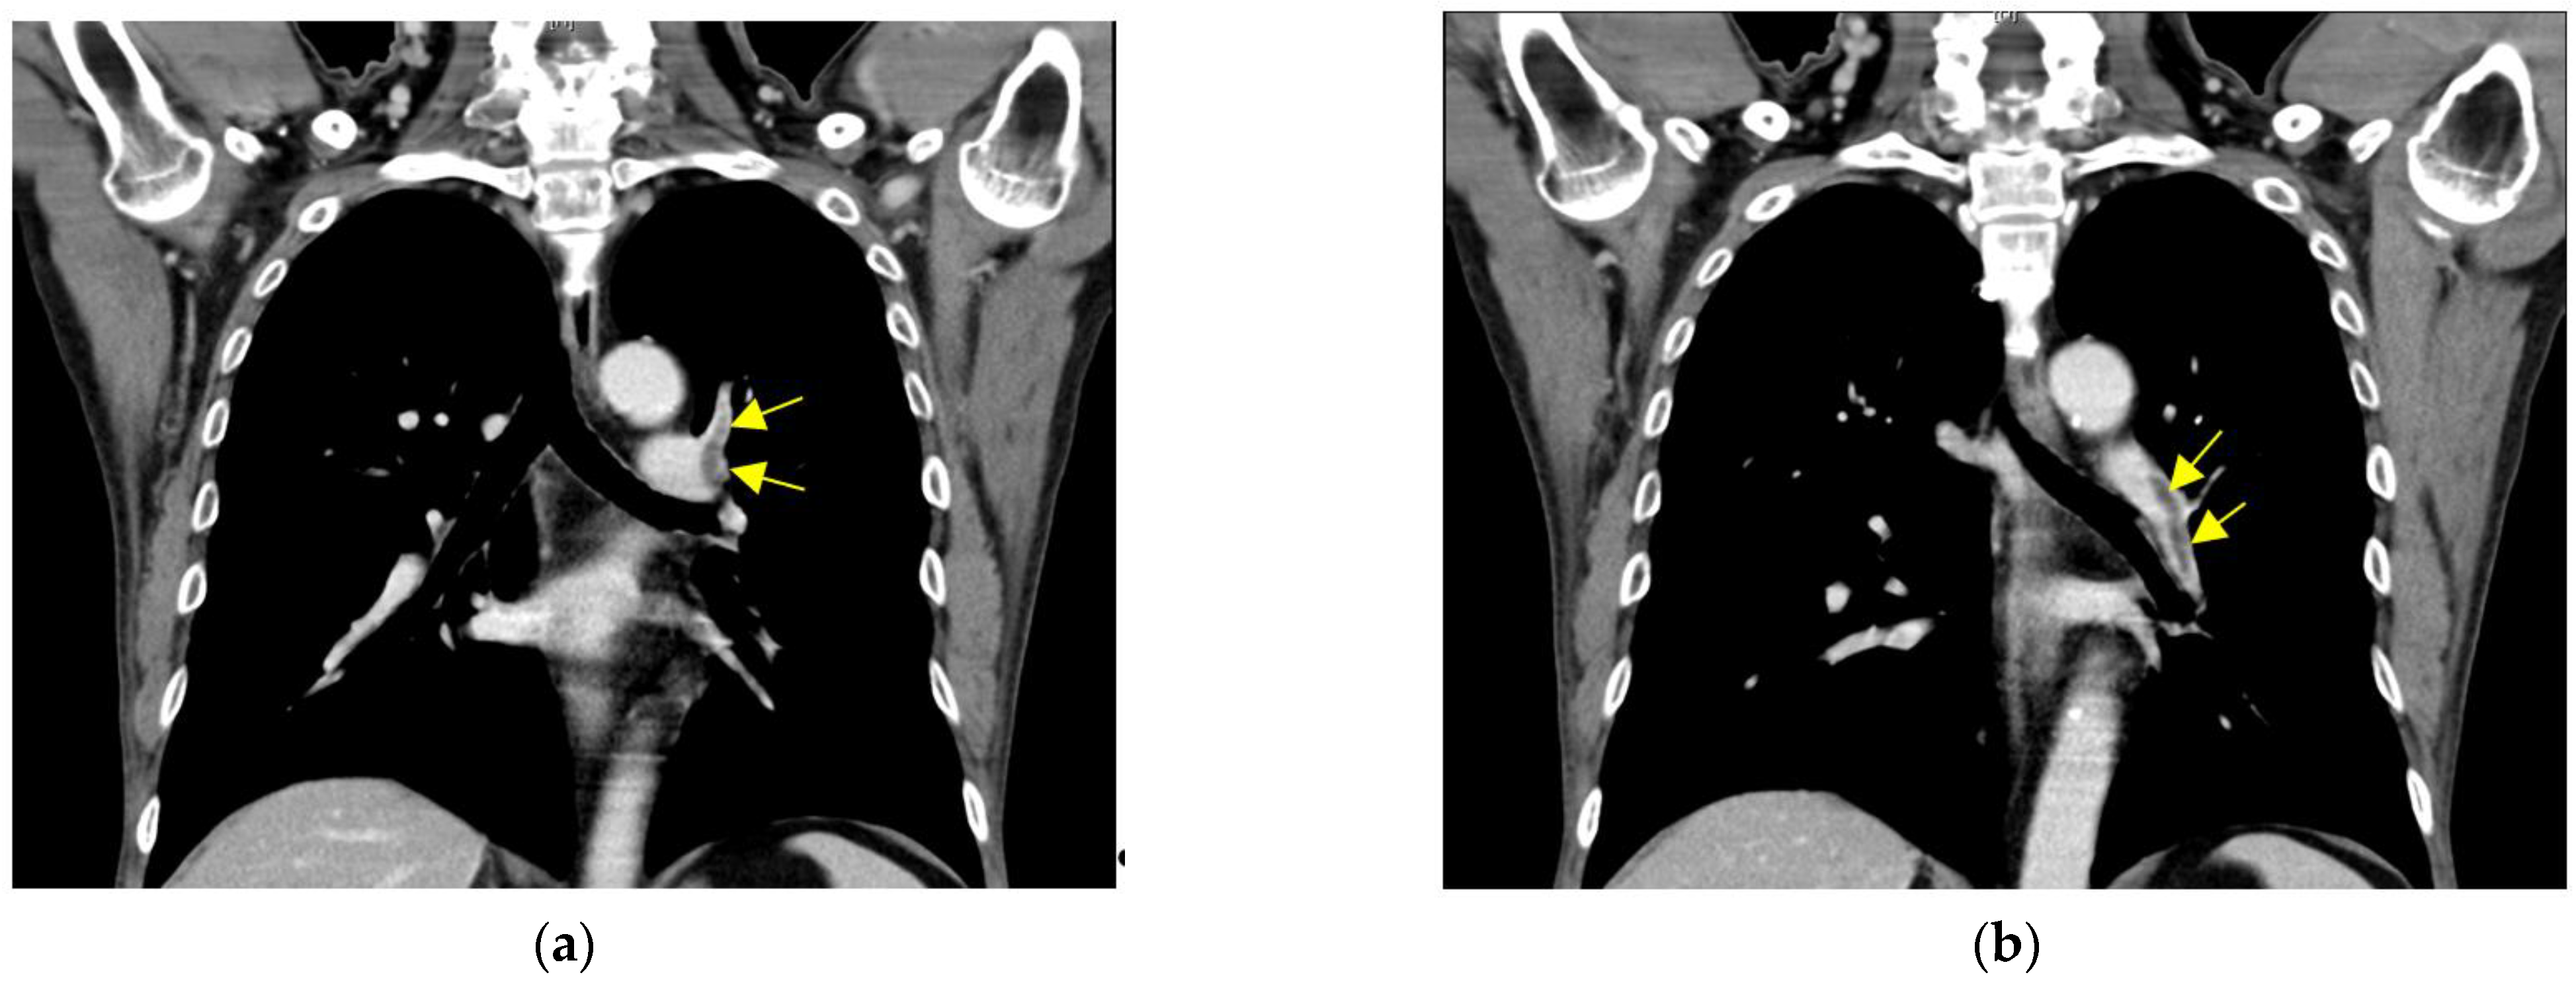

2.1. Case 1

2.2. Case 2